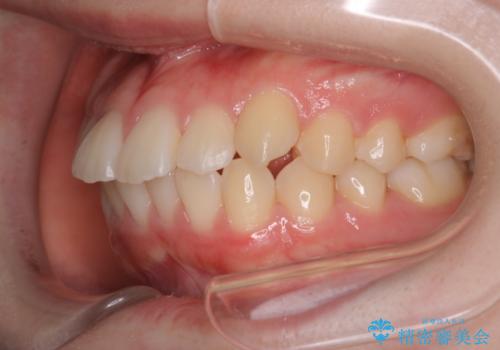

【審美装置】歯を抜いてEラインをきれいに

- 出っ歯を主訴に来院されました。今回は4番の歯を4本抜歯をし、ワイヤー矯正にて治療しました。

抜歯矯正のため2年を予定してましたが、予定よりも早く終わることができました。また口元も下がり、かみ合わせも改善しました。